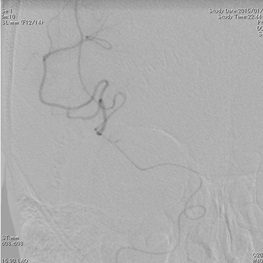

ソリティア(ステント型血栓除去器具)による超急性期血管内治療

突然の意識障害と左半身重度麻痺で発症した右内頚動脈閉塞例。発症から 5 時間が経 過しており、t-PA 治療の適応外であったため緊急で血管内治療を施行。治療開始後速やかに完全再開通を得た。術後左麻痺は残存したが意識障害は回復。